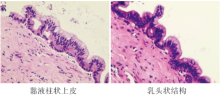

后记:2017-12-13行CT引导下胰腺肿物穿刺活检, 病理报告:送检物可见少许胰腺组织, 部分区域囊性扩张, 内衬单层黏液柱状上皮, 细胞轻度异型, 未见卵巢样间质。见图4。病理诊断:(胰腺)考虑为导管内乳头状黏液性肿瘤(IPMN)伴轻度异型增生。

吴一龙:胰腺穿刺病理中可见正常胰腺组织及病变组织, 穿刺是成功的, 病理学上目前无恶性病变证据。患者伴发胰腺、乳腺良性肿物, 目前胰腺肿物造成的梗阻已得到解除, 可动态观察。AML诊断明确, 可继续针对白血病治疗。

旁述:导管内乳头状黏液性肿瘤(IPMN)属于胰腺外分泌部肿瘤, 定义为大体可见的导管内产黏液上皮性肿瘤, 主要发生在胰腺的主胰管及分支内。根据细胞及结构异型增生的最高程度, 非浸润性IPMN分为三类:轻度、中度及重度; 出现了浸润癌的成分, 则称为IPMN相关浸润性癌。